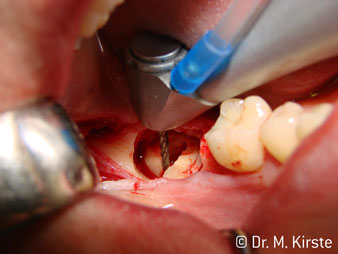

The 45° angle of the handpiece has been specially selected for its wide range of advantages. Colleagues who work in surgery, and for whom this handpiece was primarily developed, will soon appreciate the ability to work efficiently in very restricted spaces. In wisdom tooth extractions in particular (fig. 2) there is no need for large-scale spreading of the soft tissues in the cheek region (fig. 3). The design of the handpiece head combined with turning the head slightly during preparation allows work to be carried out quickly and safely in the retromolar region.

The professional design of the bearings inside the handpiece head guarantees quiet running of the bur; this makes for an impressively atraumatic cut in the separation of tooth and root (fig. 4-9).

The 45° contra-angle handpiece is very comfortable to hold. You notice almost straightaway that the working head mimics the angle of your index finger and, as such, the desired movement is simply transferred a couple of imaginary centimetres parallel to the tip. (Fig. 1)”